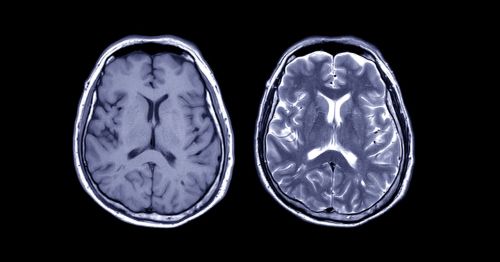

Digital twins are already used in manufacturing, industry, and aerospace. Now a European project called Neurotwin wants to make virtual copies of brains. The Neurotwin team is hoping the project can lead to treatments of neurological disorders, including epilepsy and Alzheimer’s disease.